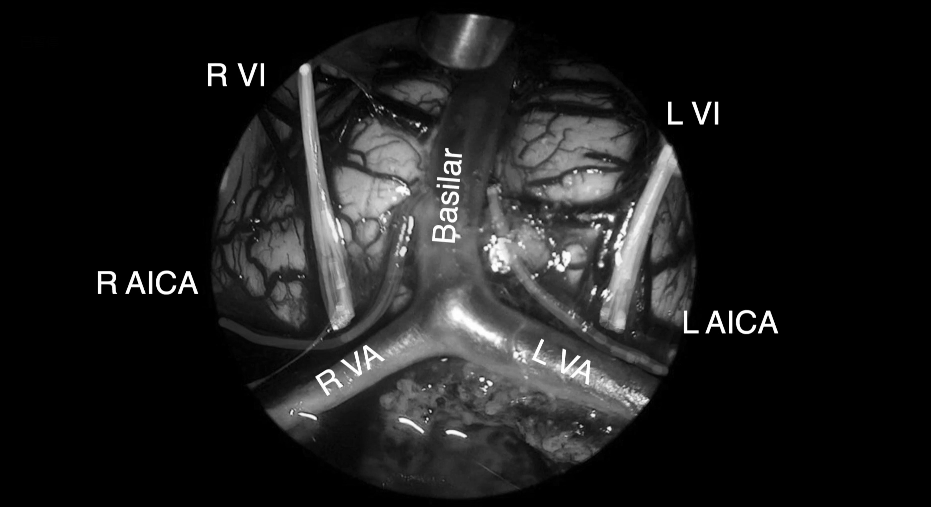

将肿瘤分离出来——Basilar Artery,基底动脉;Left VA,左侧椎动脉; Right VA,右侧椎动脉;

肿瘤取出后,可见清晰的周围血管神经。R VI,右侧展神经;LVI,左侧展神经;R AICA,右侧小脑下前动脉;L AICA,左小脑下前动脉;R VA,右侧椎动脉;LVA,左侧椎动脉;Basilar ,基底

VI,展神经;VII,面神经;VIII,前庭蜗神经;R AICA,右侧小脑下前动脉;